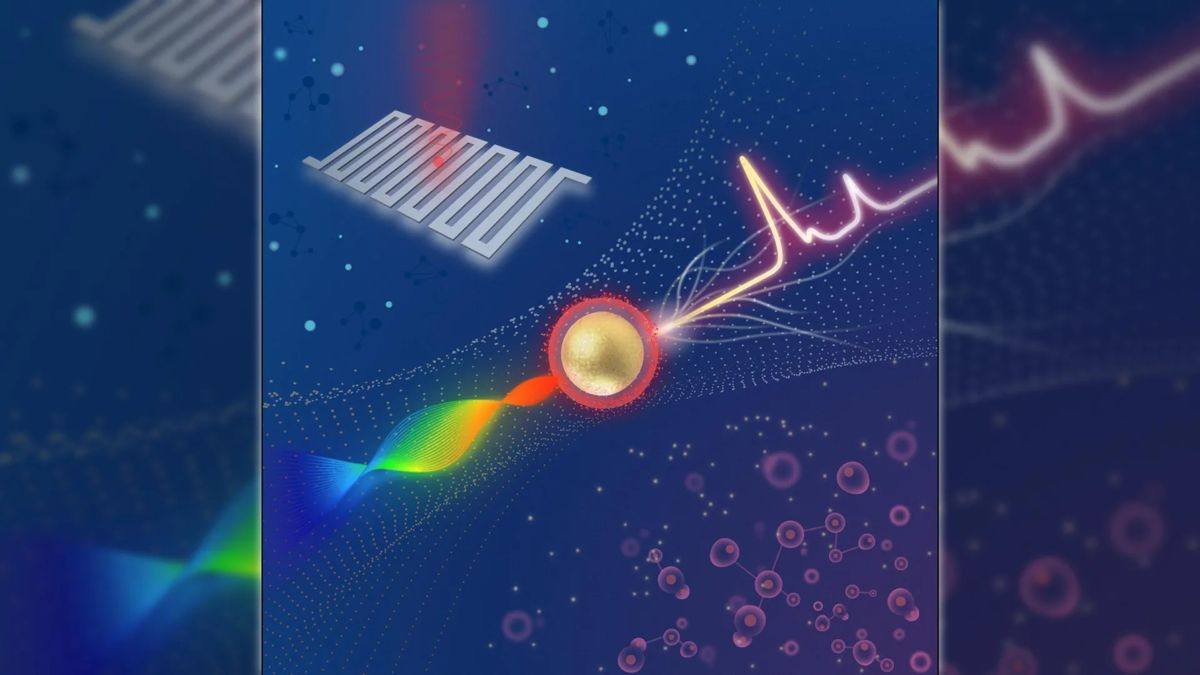

Την επανάσταση έρχεται να φέρει τώρα η GE με την ανάπτυξη του νέου υπολογιστικού τομογράφου Revolution CT ο οποίος καταγράφει εύκολα και κυρίως πάρα πολύ γρήγορα μη-συνεργάσιμα μέχρι τώρα όργανα (όπως για παράδειγμα η καρδιά) κάνοντας χρήση κάμερας πολύ υψηλής ανάλησης και σύστημα σταθεροποίησης παρόμοιο με αυτό των φωτογραφικών μηχανών. Το τελικό αποτέλεσμα είναι εξαιρετικά ακριβές και ευκρινές ακόμα και στις πιο δύσκολες περιπτώσεις ασθενών.